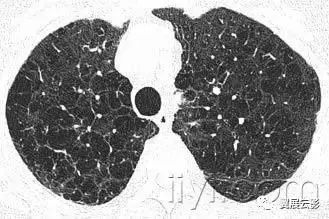

三十九、马赛克征

CT:本征象表现为不同的密度成片状镶嵌,可为间质性病变、闭塞性小气道病变(图)或者血管阻塞性疾病。马赛克征比马赛克样少血或者低灌注具有更强的诊断含义。由于支气管或细支气管阻塞导致的空气滞留可以导致局部的密度减低,在呼气相CT上表现更加明显。

该征象也可以见于间质性肺部疾病,特征是磨玻璃影,此时高密度代表间质性病变,低密度代表正常的肺。